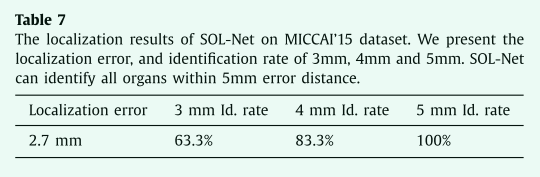

Robustness of SOL-Net and SOS-Net

小器官的分割性能可能会受到小器官定位精度的影响。如果器官边界框偏离ground truth 位置太远,则SOS-Net将很难准确地分割小器官。因此,我们进行了实验来分析我们提出的SOL-Net和SOS-Net的鲁棒性。首先,我们分析了SOL-Net的定位精度,如表7所示。对于所有小器官,SOLNet的平均定位误差 (估计质心与ground truth质心之间的平均距离) 约为2.7毫米。我们进一步测量不同距离内的小器官定位率。如果器官的估计质心与ground truth质心在一定距离内,则认为该器官已正确定位。63.3% 的小器官位于3毫米内,83.3% 可以位于4毫米内。如果我们将距离扩展到5毫米,所有小器官都可以正确定位。

表7 SOL-Net在miccai'15数据集上的定位结果。我们给出了定位误差,以及3毫米、4毫米和5毫米的识别率。SOL-Net可以识别5毫米误差距离内的所有器官。